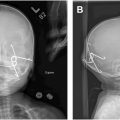

This is a more common craniofacial cleft and results from the failed fusion of the medial nasal processes ( Figs. 3 and 4 ). The medial nasal processes merge at the midline in week 6 to form the centralized midface structures: nasal tip, columella, philtrum, and premaxilla. As such, presentation typically includes a bifid nose with either deficient or excess midline structures. In severe cases, the nasal tip is absent and the nostrils are completely separate, causing significant orbital hypertelorism. This may also appear with absent anterior lip, nasal bones, and premaxilla resulting in cleft palate. When hyperplastic, the nasal septum can be thickened or duplicated with a flat or furrowed nasal dorsum, short and wide columella, and widened forehead with hypertelorism. It may uncommonly present with frontonasal encephalocele, holoprosencephaly, or a range of mental disabilities. A continuation superiorly as a number 14 cleft is also possible.